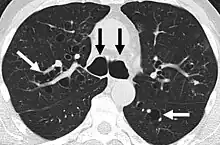

A chest x-ray is abnormal in most patients with bronchiectasis. Computed tomography is recommended to confirm the diagnosis and is also used to describe the distribution and grade the severity of the disease. Radiographic findings include airway dilation, bronchial wall thickening, and atelectasis.[3]

-

Bronchiectasis primarily in the middle lobe of the right lung. -

Bronchiectasis secondary to a large carcinoid tumor (not shown) that was completely obstructing the bronchus proximally. Dilation of the airways is present.